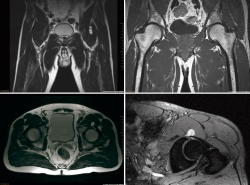

Presentamos el caso de un varón de 48 años, instructor de tenis profesional, sin antecedentes clínicos relevantes. Consulta por coxalgia izquierda incapacitante durante la actividad laboral de unos 18 meses de duración. El examen físico mostró dolor en flexión y rotación interna de la cadera izquierda y una prueba de choque positiva. Se realizaron radiografías para evaluar la presencia de morfologías que pudieran predisponer a un pinzamiento femoroacetabular (Figura 1). No se observó morfología anormal o signos de osteoartritis. El tratamiento inicial incluyó la prescripción de antiinflamatorios no esteroideos (AINE) y la modificación de la actividad física. Se realizó una resonancia magnética (RM) para completar el estudio. Los resultados de la RM no identificaron alteraciones morfológicas o cambios de señal en la cabeza femoral que pudieran sugerir necrosis ósea, focos de osteocondritis, fracturas por estrés, edema óseo u osteoporosis transitoria. Se identificó una lesión del labrum anterior con un quiste paralabral asociado a esta, de 32 × 17 mm (Figura 2). Después de 3 meses de tratamiento conservador sin mejoría clínica, se propuso la escisión quirúrgica y la reparación del labrum. La extirpación quirúrgica se realizó a través de artroscopia mediante técnica fuera-dentro. Todas las estructuras óseas en el compartimento central no mostraron signos patológicos. Se observó una lesión del labrum en su zona anterosuperior (zona 2)(2). En el compartimento periférico, se identificó una gran lesión quística que rodeaba el borde anterosuperior del labrum y el acetábulo (Figura 3). La extirpación completa del quiste se realizó artroscópicamente utilizando material específico para la artroscopia de cadera. No se registraron complicaciones intraoperatorias. La reparación labral se realizó con un sistema de anclaje All-Suture® de tipo Y-Knot® (Conmed). Se inició el protocolo de fisioterapia postoperatoria habitual de nuestro centro, permitiendo la carga parcial con dos muletas al momento del alta con progresión gradual a peso completo en un periodo de 2-3 semanas, seguido de un protocolo de rehabilitación para conseguir el rango completo de movilidad articular y lograr la fuerza completa de la extremidad. En un periodo de 3 meses, el paciente regresó por completo a la actividad física. No se observaron complicaciones.

Figura 1. Radiografía anteroposterior y lateral preoperatoria de la cadera izquierda.